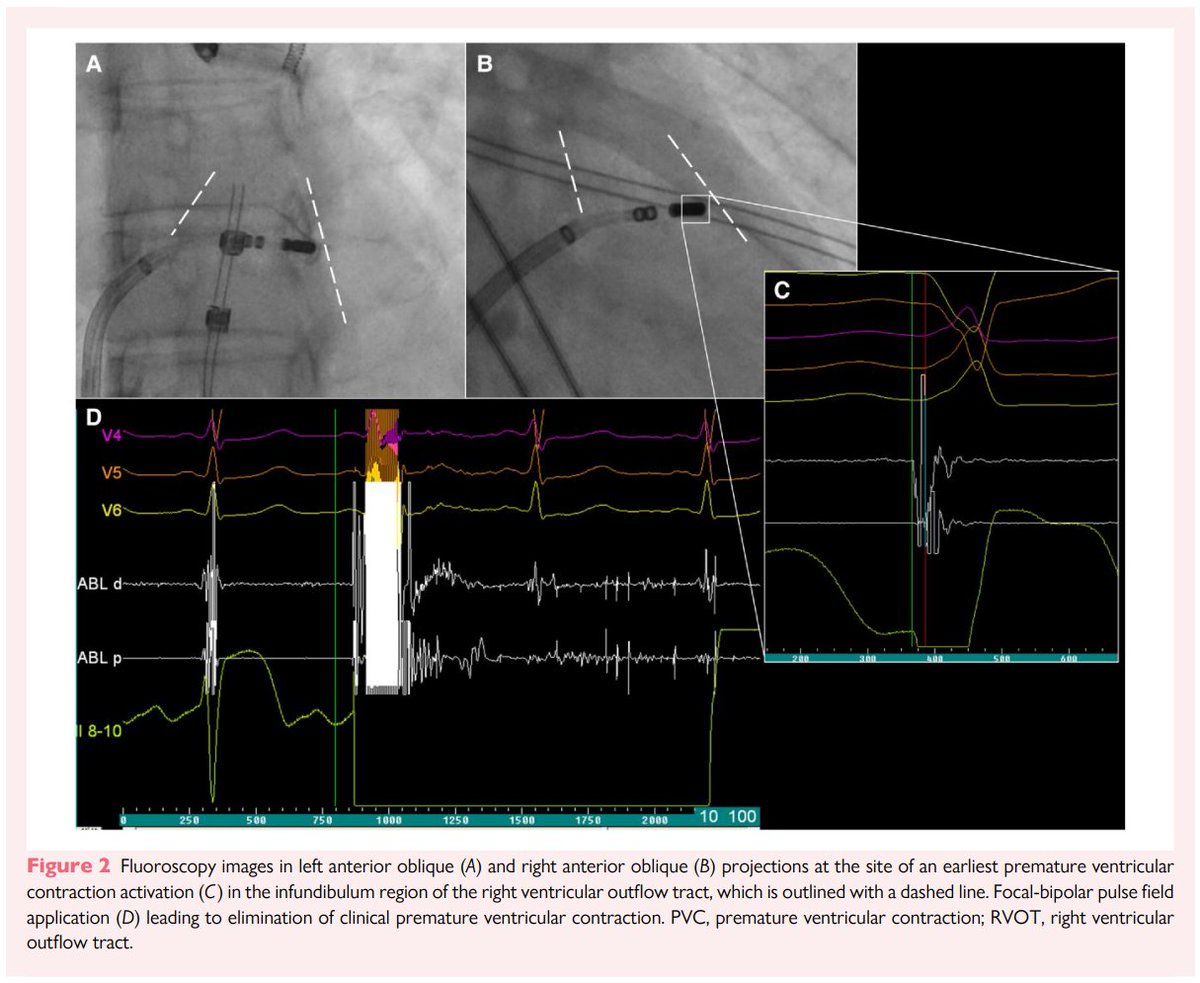

Have you ever tackled a tough RVOT PVC case with an abrupt precordial transition zone in V4? Focal-bipolar pulsed field ablation (PFA) can work in the infundibular zone of the anteromedial RVOT. Anatomical image courtesy Prof. Kalyanam Shivkumar (Amara-Yad Project).